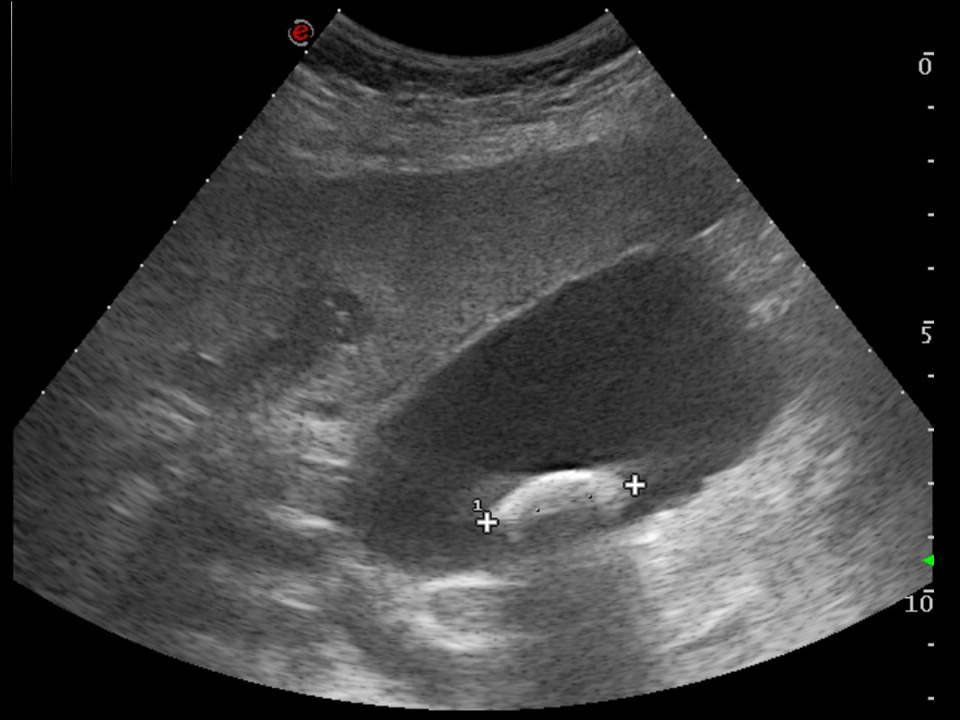

FAST / eFAST sonography

Frequently, the first imaging method for a severly injured patient is sonography. The “FAST” acronym stands for “Focused Assessment with Sonography in Trauma” which refers to the speed of the examination which should not exceed 2 minutes as stated by the protocol. During the examination, specific areas (epigastric area, right and left side, pelvic area) are examined to exclude pericardial, pleural and abdominal free fluid any of which may arise from injury to the vessels or parenchymal organs.

• Rupture and contusion of the parenchymal organs. The affected organ is usually already detected on US however, only CT can give definitive diagnosis, e.g. when the organs are covered by bowel gases. With US the liver the spleen the kidneys can be well examined, although the pancreas frequently could not be visualized, as it is covered by meteorism. Furthermore, US might not be able to detect injuries of parenchymal organs when the capsule of the organ is not ruptured. When evaluating the CT scan of the polytrauma patient the grade of severity is usually defined by the AAST (American Association for Surgery of Trauma) classification specified for each organ.

• Sometimes, the presence of a right subcostal radiopaque stone on a plain abdominal radiograph can confirm the suspicion of cholelithiasis, cholecystitis. The method of choice however, is ultrasonography. US examination can depict stones located either in the gall bladder or in the biliary tract. They are shown as hyperreflective structures with acoustic shadowing. As a sing of inflammation the bladder wall thickens, becomes multilayered and edematous. Doppler examination can reveal the consequent hypervascularization of the inflammation. When US is unable to examine the extrahepatic biliary ducts, CT will not provide additional information because the choleliths might not be radiopaque. In these cases MRCP might be indicated.

17. Typical right subcostal colic pain. Ultrasound examination. On the right is a typical picture of a cholelith with acoustic shadowing. The left image shows cholecystitis with multilayered, edematous and hypervascularized gall bladder wall. Note the intraluminal dense sludge and the presence of multiple, small gallstones.